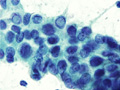

- (4)Aspiration biopsy cytology of thyroid gland (papillary carcinoma)

The nuclei of cancer cells showed ground-glass appearance and the intranuclear cytoplasmic inclusions (arrow). (Giemsa stain)